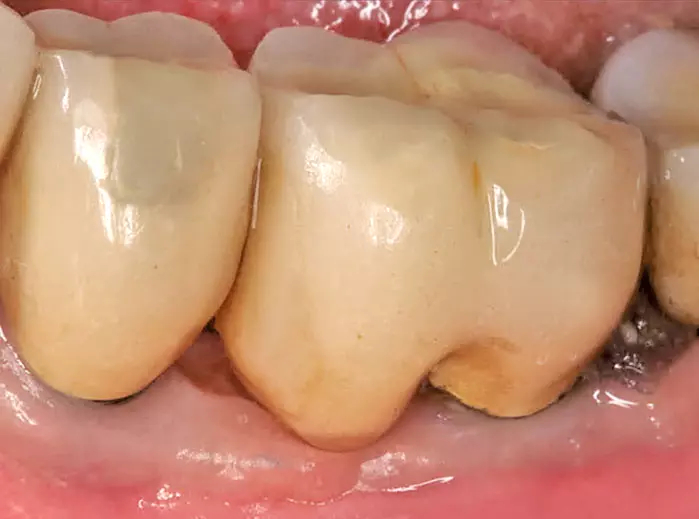

Auch diese signifikante Erhöhung des Periimplantitisrisikos bezieht sich auf Bone-Level Implantate, nicht aber auf Tissue-Level Implantate. Es scheint, dass die reduzierte Hygienefähigkeit und die damit verbundene erhöhte Plaqueakkumulation für die erhöhte Periimplantitisprävalenz von Implantaten, die mit Abutments mit weitem Emergenzwinkel und konvexem Emergenzprofil versorgt sind, verantwortlich sind [11].

Was hat die bisher dargestellte Evidenz für einen Einfluss auf unsere tagtägliche Therapie? Die Implantatposition, seine Angulation, die Weichgewebsdicke und der gewählte Diameter haben einen Einfluss auf sowohl Emergenzwinkel als auch Emergenzprofil. Somit werden die genannten Parameter nicht nur durch das Team Prothetiker und Zahntechniker, sondern maßgeblich durch Weichgewebsdicke und Implantatposition bestimmt. Daher sollte die aufgeführte Evidenz nicht nur dem Prothetiker, sondern vor allem auch dem Chirurgen bekannt sein, denn bereits bei der Chirurgie wird der Grundstein für die Abutmentgestaltung gelegt.

Der in Abbildung 4 gezeigte Emergenzwinkel und Emergenzprofil ist zum einen der Weichgewebshöhe als auch der Implantatposition geschuldet. Bei solchen Situationen, die häufig im Unterkierferseitenzahnbereich auftreten, muss sich der Chirurg vor der Implantation folgende Gedanken machen:

Ist die vorhandene Weichgewebshöhe nicht hoch genug um einen Emergenzwinkel von <30° und ein konkaves Emergenzprofil zu gewährleisten, muss die Frage nach der weichgewebigen Augmentierbarkeit gestellt werden.

Ist die gewünschte Weichgewebshöhe durch weichgewebige Augmentation nicht vorhersagbar zu realisieren, so muss über die optimale Implantatposition nachgedacht werden.

Sind, bei ausreichender Weichgewebshöhe, aufwendigere chirurgische Maßnahmen zur mittigen Implantatpositionierung erstrebenswert (Abb. 5), kann diese bei niedriger Weichgewebshöhe zu einem ungünstig großen Emergenzwinkel wie in Abbildung 4 führen.